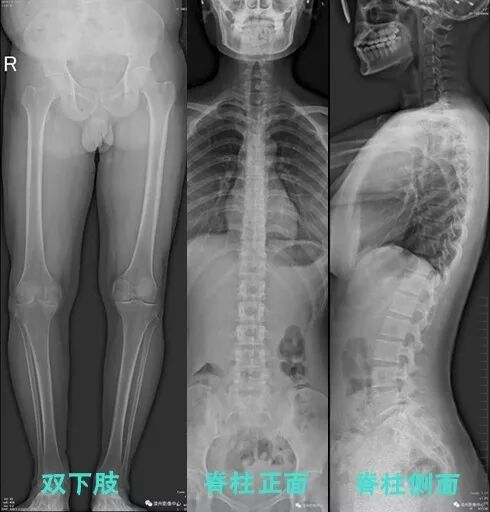

灤州市人民醫(yī)院大影像科引進日本島津數(shù)字胃腸機,目前已開展全脊柱及雙下肢全長拼接攝影技術(shù)”,并投入臨床使用。此技術(shù)可在一幅X光圖像上完整顯示全脊柱或雙下肢整體形態(tài),射線劑量小,圖像清晰度高,誤差小于1毫米,為臨床在脊柱側(cè)彎畸形和下肢骨關(guān)節(jié)病變診斷、治療方案制定及治療后復查提供精準的測量。

全脊柱攝影,能清晰顯示全脊柱的全貌,為骨科臨床診治脊柱側(cè)彎畸形、負重骨骼矯形提供了高質(zhì)量的影像資料,有效滿足臨床診斷和治療的要求。

下列圖片能夠清晰對比出傳統(tǒng)與新技術(shù)的區(qū)別:

全脊柱及雙下肢拼接攝影技術(shù)影像